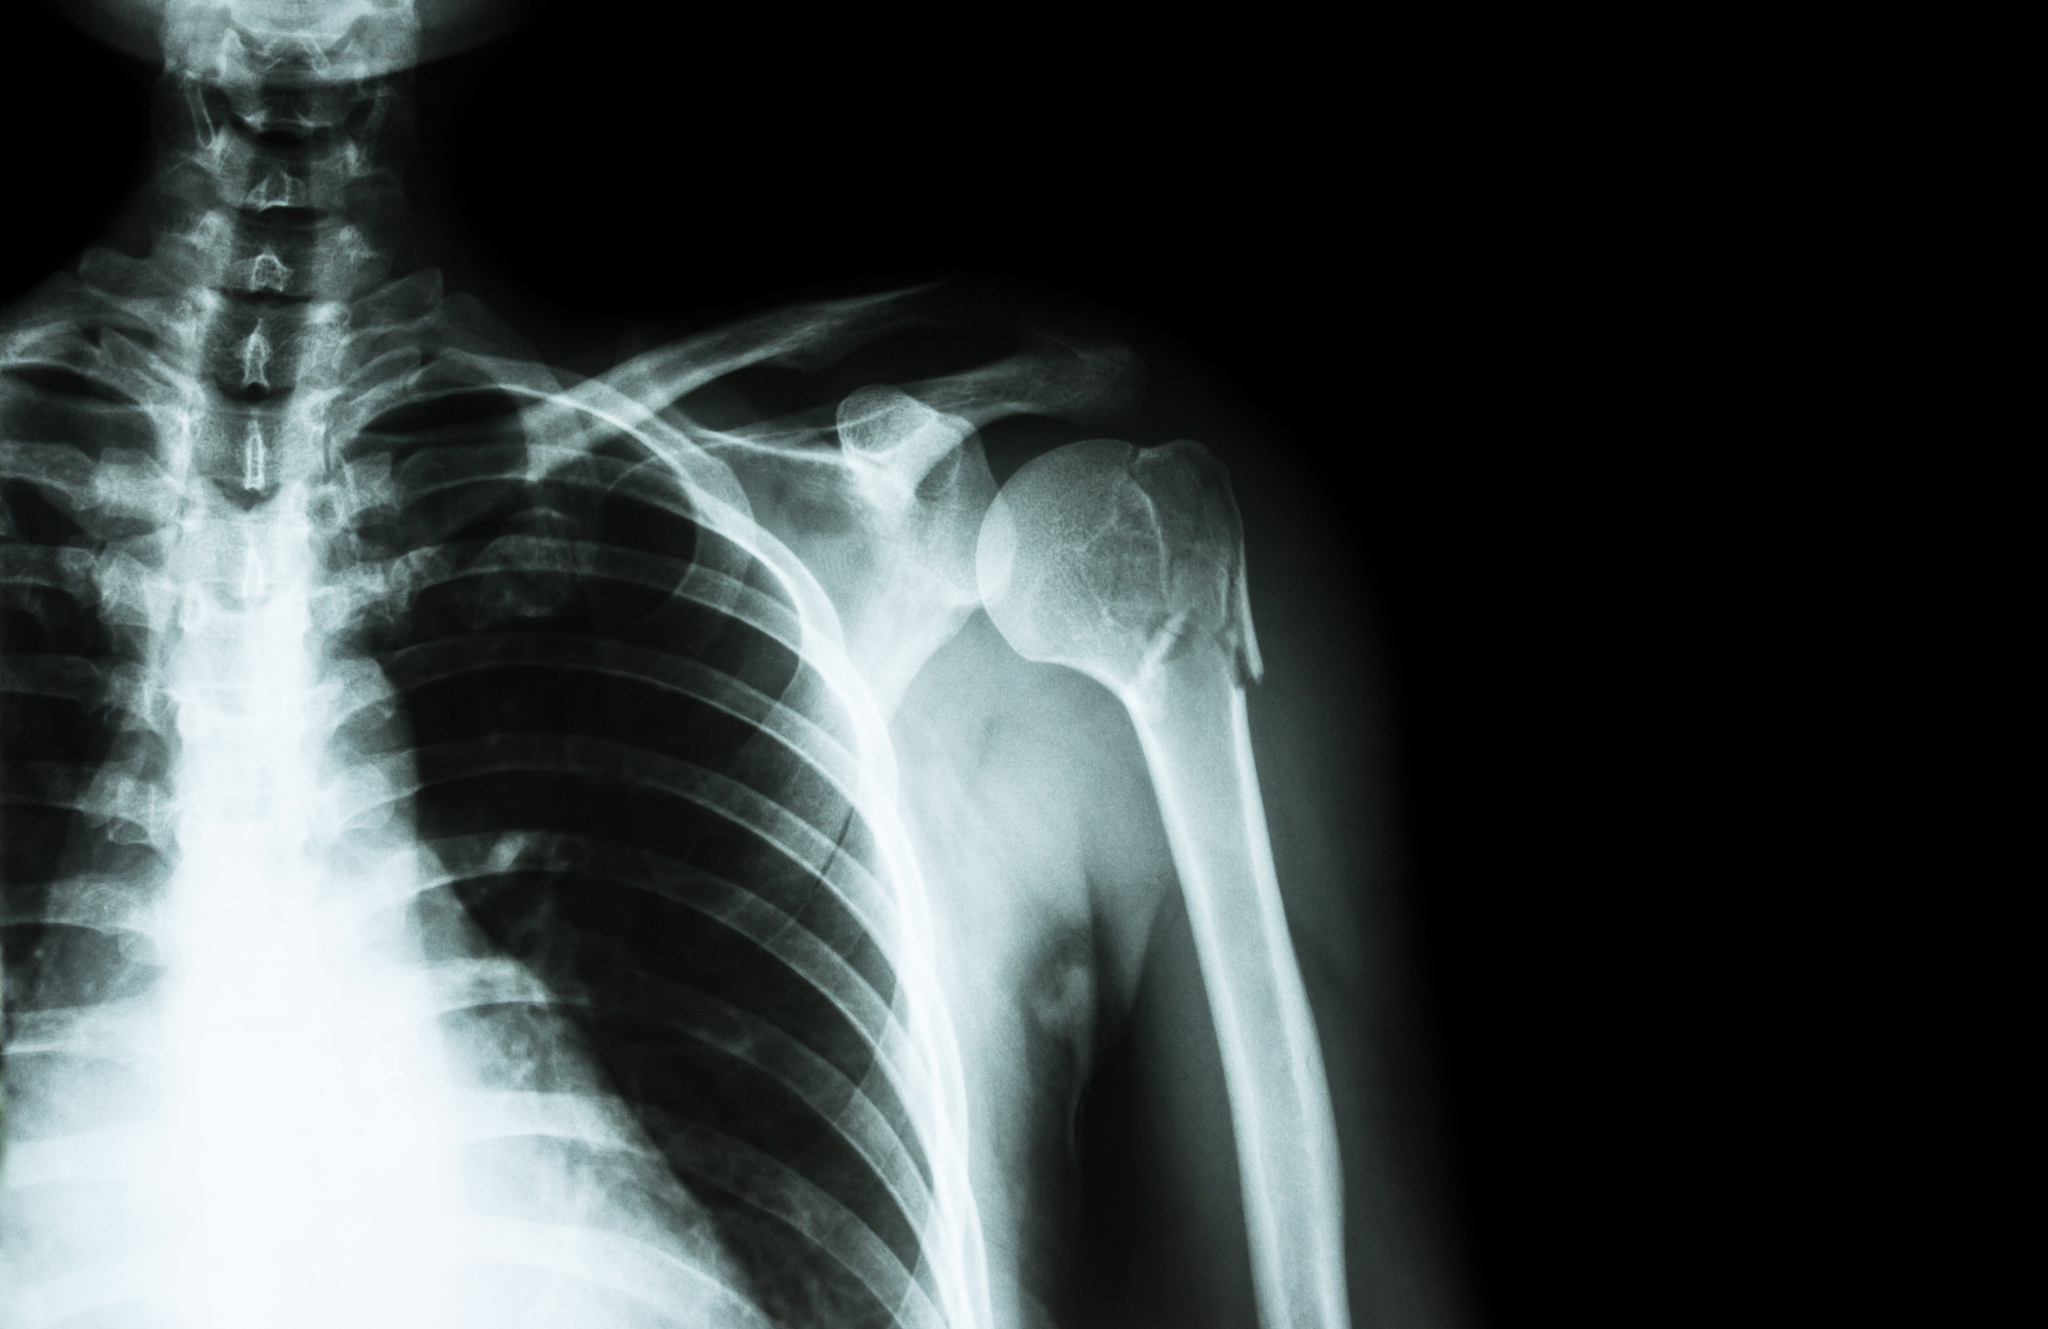

肱是人体上臂的一部分,位于肩膀和肘部之间。肱骨、尺骨和桡骨组成了人体上臂的骨架结构,肱二头肌、肱三头肌、肩袖肌群等肌肉则负责人体上臂的运动。

肱部的疾病包括肱骨骨折、肱骨头坏死以及肱骨滑囊炎等。肱骨骨折一般由外力打击导致,常见于运动员和老年人。肱骨头坏死则是由于肱骨头的供血不足而引起的骨质坏死。肱骨滑囊炎则是由于肩袖肌群的过度使用而引起的肩部疼痛。